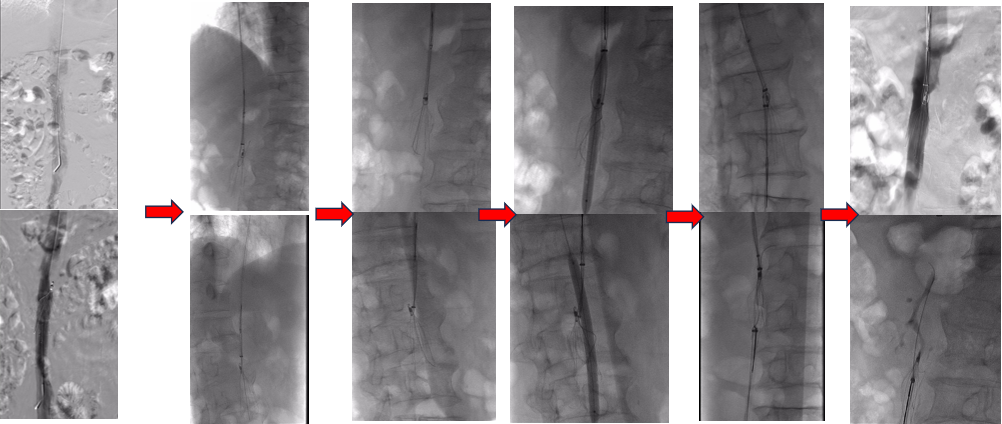

图为:入院后再次尝试腔内回收滤器,经4h努力以失败告终